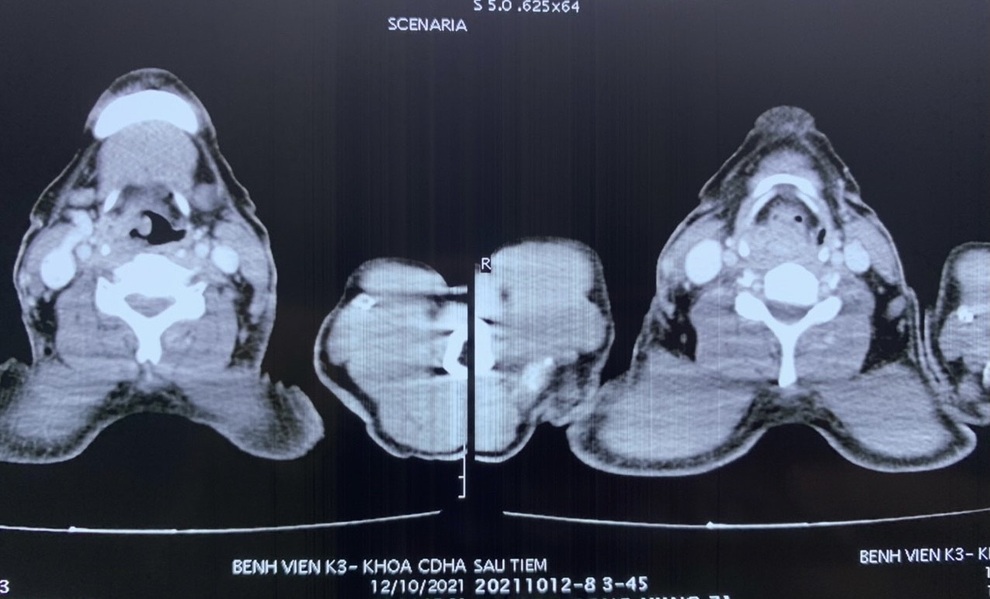

Khi đi khám tại Bệnh viện K, bác sĩ chẩn đoán ông Nguyễn Công H. ung thư hạ họng giai đoạn cuối, di căn thực quản, phải thực hiện ca phẫu thuật lấy khối u và tái tạo đường ăn để có thể ăn uống bình thường sau điều trị ung thư.

Tại Bệnh viện K, các bác sĩ xác định bệnh nhân u ác hạ họng di căn thực quản giai đoạn cuối.

"Cụ H.có u lớn vùng xoang lê phải, lan xuống vùng miệng thực quản, kết quả giải phẫu bệnh ung thư tế bào vẩy(SCC), giai đoạn 4 , T3N1M0. Vì khối u ngày càng phát triển, nếu không đưa ra quyết định sớm để điều trị thì sẽ khiến chất lượng sống của bệnh nhân bị ảnh hưởng nghiêm trọng và sức khỏe chắc chắn sẽ diễn biến xấu hơn", TS.BS Phạm Văn Bình, Phó Giám đốc chuyên môn Bệnh viện K, Trưởng khoa Ngoại bụng 1 cho biết.

Với bệnh nhân này, trên nền bệnh nhân tuổi cao, ung thư miệng thực quản và 1/3 trên thực quản, đã tiến triển lan rộng, các bác sĩ quyết định phẫu thuật lấy khối u, nạo vét hạch và tạo một đường ăn cho bệnh nhân, giúp nâng cao chất lượng cuộc sống sau điều trị.